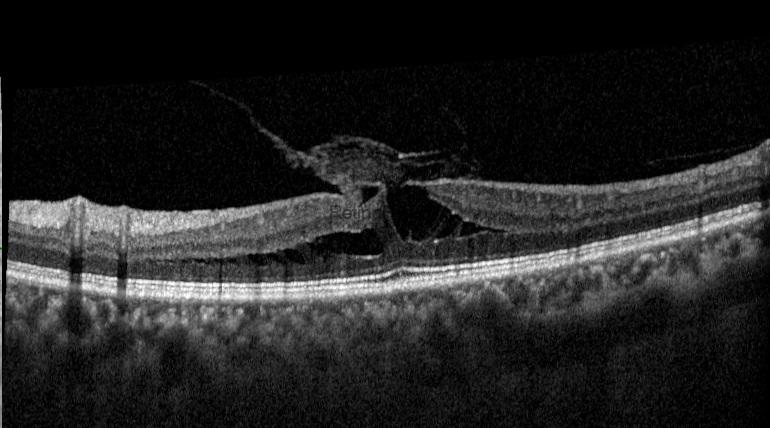

This post will present a Tractional Lamellar Macular Hole surgery. This is a 55-year-old female patient whose left visual acuity has been decreasing over the last 6 months. Her preoperative visual acuity was 20/100. OCT revealed a vitreomacular traction, a Tractional lamellar macular hole (LMH), a thin ERM at the edge of LMH, and a thick fibroglial tissue. The term tractional LMH has recently been changed to ERM-Foveoschisis. However, because the traction of the vitreous and fibroglial tissue on the fovea is the primary concern in this case, it would be more accurate to refer to it by the older term.

Preoperative multicolor image, autofluorescence image, and OCT of the patient with a tractional macular hole

The surgeon performed a combined vitrectomy with cataract surgery in this case. She used the Eibos 2 imaging system and the Dorc Eva faco-vitrectomy device. One month after surgery, foveoschisis or LMH disappeared, and a complete foveal depression occurred.